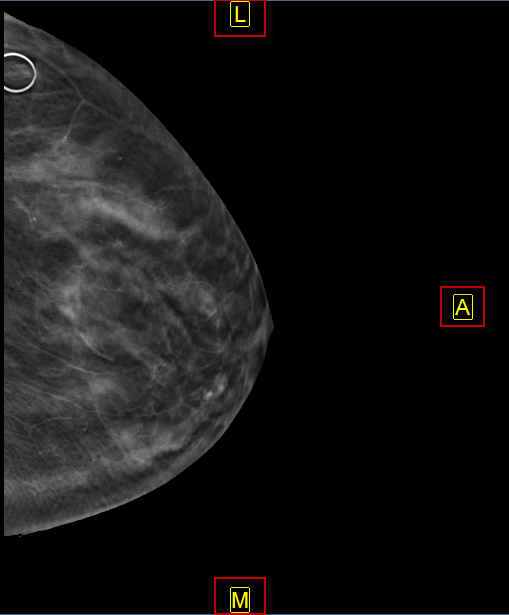

The images below represent a sinus CT and a Mammography that have Auto-Orientation applied.

The auto orientation feature overrides the default patient orientation, as defined by the modality, and applies a user-defined orientation. When auto orientation is applied to an image, the patient orientation markers are force to appear on the image and are displayed in yellow.

- P/A sets the posterior (P) or anterior (A) side of sagittal and mammography images to the right edge of the image frame.